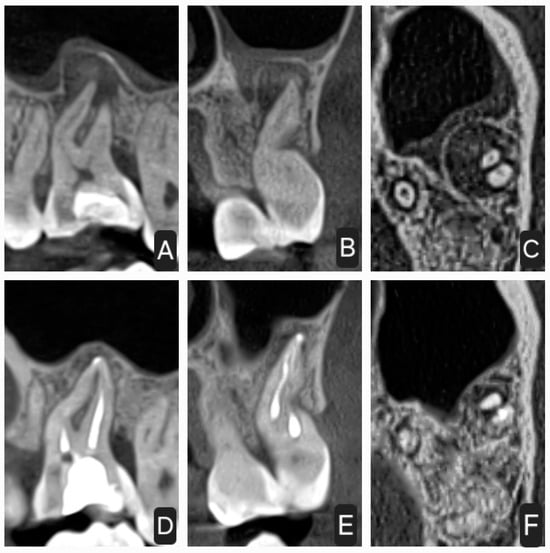

2.1. First Case

2.2. Second Case

2.3. Third Case